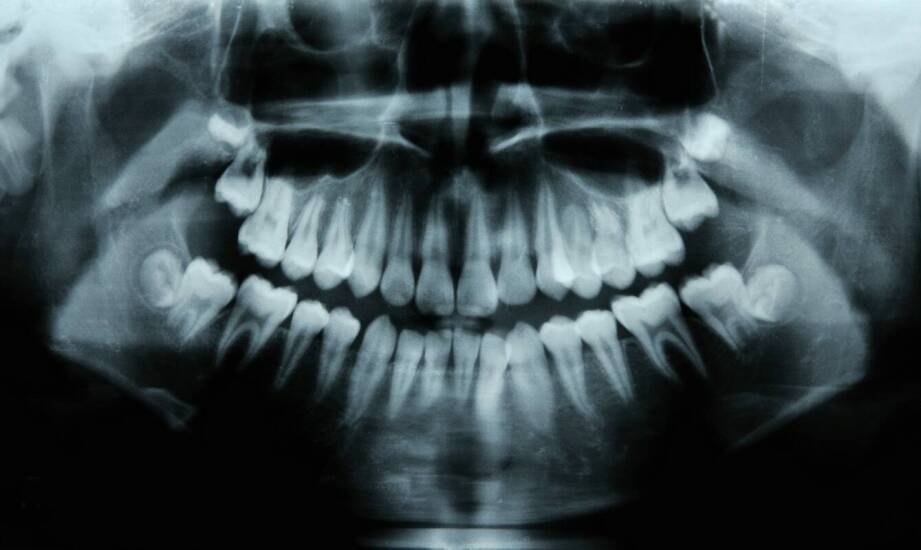

Tomografia stożkowa (CBCT) tworzy trójwymiarowy model struktur zębów, kości szczęk, tkanek przyzębia i zatok szczękowych. Urządzenie wykonuje serię skanów, a oprogramowanie składa je w dokładny obraz 3D, który można dowolnie obracać i powiększać. Dzięki temu dentysta ocenia miejsca niedostępne na standardowych zdjęciach rentgenowskich.

CBCT umożliwia lekarzowi dostrzeżenie drobnych zmian, które umykają na zdjęciach 2D. W praktyce oznacza to wcześniejszą diagnozę i bezpieczniejsze leczenie.

Najczęstsze wskazania i wykrywane nieprawidłowości:

- Próchnica i zmiany pod wypełnieniami – w tym wtórna próchnica i nieszczelności trudne do oceny w 2D.

- Zmiany okołowierzchołkowe, torbiele, ropnie, łagodne i złośliwe guzy kości.

- Pęknięcia i złamania korzeni, resorpcje wewnętrzne i zewnętrzne.

- Ocena kanałów korzeniowych – dodatkowe kanały, nietypowa anatomia, stopnie zakrzywienia.

- Choroby przyzębia – ubytek kości, defekty ścian, furkacje.

- Urazy – przemieszczenia, złamania wyrostków, ocena gojenia.

- Wady zgryzu i zęby zatrzymane – dokładne położenie względem nerwów i zatok.

- Zatoki szczękowe – pogrubienia błony śluzowej, zastoje, polipy kontaktujące z korzeniami.

Trójwymiarowy obraz pozwala precyzyjnie ocenić rozmiar i położenie zmian, gęstość i objętość kości oraz relacje do struktur krytycznych, takich jak kanał nerwu zębodołowego dolnego czy dno zatoki szczękowej. Dzięki temu lekarz ogranicza ryzyko powikłań, szybciej stawia diagnozę i planuje zabiegi z większą przewidywalnością. W wielu sytuacjach CBCT zastępuje kilka odrębnych zdjęć 2D, skracając ścieżkę diagnostyczną.